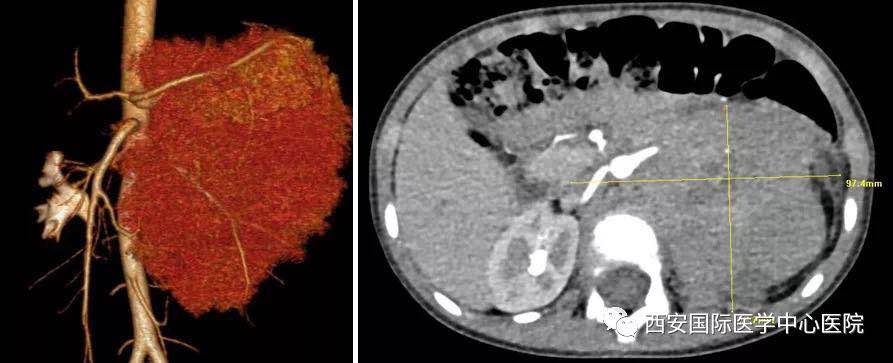

入院后,楊增悅主任仔細(xì)詢問(wèn)病史、查閱影像學(xué)資料,第一時(shí)間為依依安排骨髓穿刺活檢,最終確診為:腹膜后神經(jīng)母細(xì)胞瘤(Ⅳ期/L2)。CT顯示腫瘤巨大,侵及腹主動(dòng)脈、腹腔干、腸系膜上動(dòng)脈、雙腎動(dòng)脈、腸系膜下動(dòng)脈、下腔靜脈、雙腎靜脈、左腎及腎上腺、胰十二指腸、脾臟、結(jié)腸脾曲;腹膜后多發(fā)淋巴結(jié)轉(zhuǎn)移、骨轉(zhuǎn)移。骨穿病檢示:神經(jīng)母細(xì)胞瘤骨髓轉(zhuǎn)移,腫瘤細(xì)胞占90.5%。經(jīng)過(guò)科室團(tuán)隊(duì)討論后決定,先行新輔助化療后再進(jìn)行手術(shù)治療。